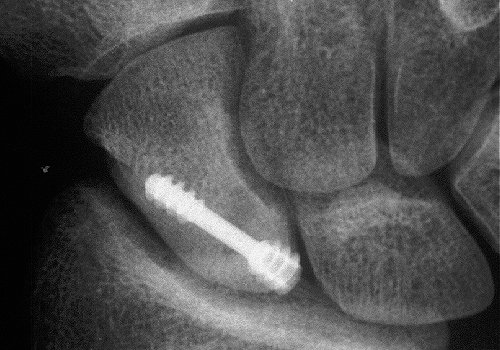

The problem: minimally displaced proximal pole scaphoid fracture three weeks post injury. Although this appears relatively innocuous, it actually has a significant chance of nonunion despite prolonged immobilization.

Xray before

Click for larger image